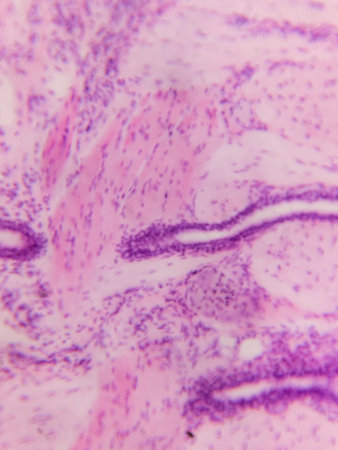

A microscopic view of tissue with pink and purple staining, showing cellular structures and patterns

Microscopic view of tissue with purple and pink staining, showing cellular structures and nuclei